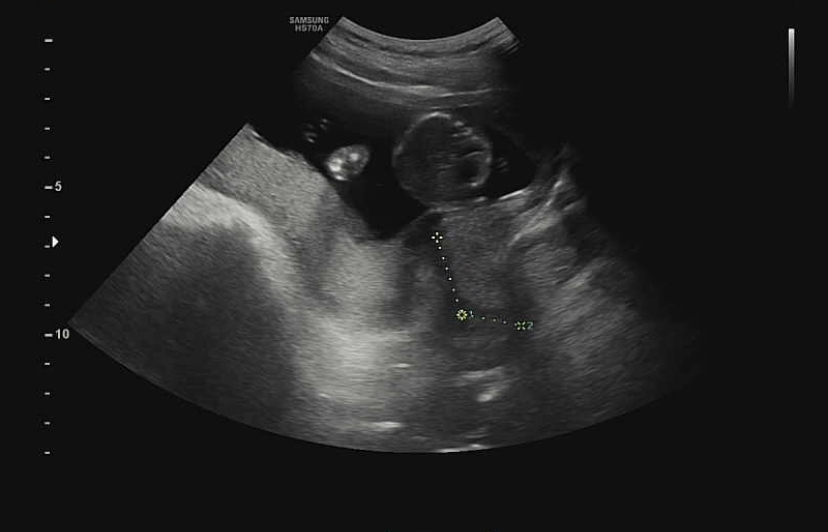

지난 초음파 영상을 보면서 처음에 재는 길이가 뭘까 했는데 자궁경부 길이라고 설명해주셨다.자궁경부 길이가 너무 짧으면 조산 위험이 있고 임신부 사이에서는 ‘눕는다’고 알려진 절대 안정을 취해야 한다.

이 경우 밥 먹을 때 말고는 앉아 있을 수도 없다고 하니 엄마가 되는 게 정말 쉽지 않다.